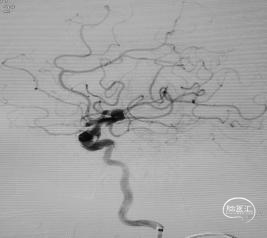

造影所示:患者左侧颈内动脉分叉部动脉瘤,大小约11mm*10mm,合并左侧颈内动脉终段、海绵窦段和岩骨段蛇形动脉瘤。动脉瘤形态复杂、不规则、体积大且长。大脑前动脉和大脑中动脉从分叉部动脉瘤上发出,压颈无代偿,采用微导管保护下瘤内扰流装置是比较理想的治疗策略。其近端蛇形动脉瘤,采用桥接血流导向装置能够达到较好的治疗效果。且已有研究表明,血流导向装置联合瘤内扰流装置治疗颅内复杂大型动脉瘤在技术上是可行的,且可能尽早地将动脉瘤闭塞。因此,经全科慎重讨论,本案例采用桥接血流导向装置+瘤内扰流装置植入术的治疗方案。

造影观察血流及支架展开及贴壁情况。

撤出微导管后造影见左侧大脑中、大脑前动脉显影,血流通畅。